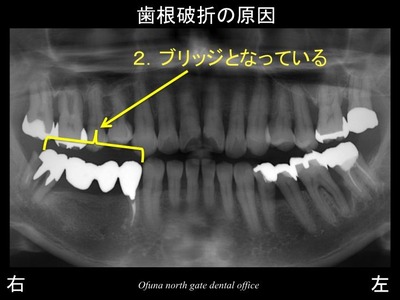

以下は初診時のレントゲンです。

この歯は歯根破折 していました。

この歯は、抜歯になります。

歯根破折の原因:1

歯根破折の原因:2

ブリッジの土台となっている

ブリッジは、欠損部の両側の歯を土台として

欠損部を補うように被せ物を装着する治療法です。

そのため、ブリッジの土台となる歯には欠損部の力が加わりますので、非常に負担になります。

この負担によりブリッジはダメになることがあります。

これらをまとめると

今回歯根破折 した原因は、

歯が2歯分欠損しており、

それを支える土台となる歯が神経がないために

神経がない歯に加重負担が加わり ダメになったのです。

これは当然の結果です。

ブリッジを行った始めの段階で このような結果はすでに分かっていたことなのです。